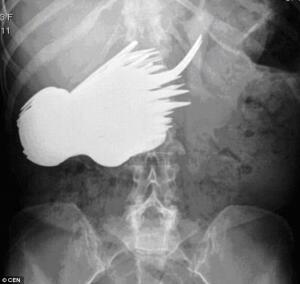

А это после операции. И денег не надо за операцию. Все столовое серебро.

Женщина страдала навязчивой идеей "поедать" серебряные вилки и ложки, не психическим расстройством а идеей. И вот, что на рентгенограмме.